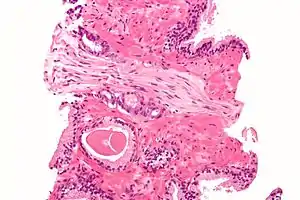

Biopsy

If cancer is suspected, a biopsy is offered expediently. During a biopsy, a urologist or radiologist obtains tissue samples from the prostate via the rectum. A biopsy gun inserts and removes special hollow-core needles (usually three to six on each side of the prostate) in less than a second. Prostate biopsies are routinely done on an outpatient basis and rarely require hospitalization.

Histopathologic diagnosis

A histopathologic diagnosis mainly includes assessment of whether a cancer exists, as well as any subdiagnosis, if possible. Histopathologic subdiagnosis has implications for the possibility and methodology of Gleason scoring.[85] The most common histopathological subdiagnosis is acinar adenocarcinoma, constituting 93% of diagnoses.[86] The most common form of acinar adenocarcinoma, in turn, is "adenocarcinoma, not otherwise specified", also termed conventional, or usual acinar adenocarcinoma.[87]

After a biopsy, a pathologist examines the samples under a microscope. If cancer is present, the pathologist reports the grade of the tumor. The grade tells how much the tumor tissue differs from normal prostate tissue and suggests how fast the tumor is likely to grow. The pathologist assigns a Gleason number from 1 to 5 for the most common pattern observed under the microscope, then does the same for the second-most common pattern. The sum of these two numbers is the Gleason score. The Whitmore-Jewett stage is another method.